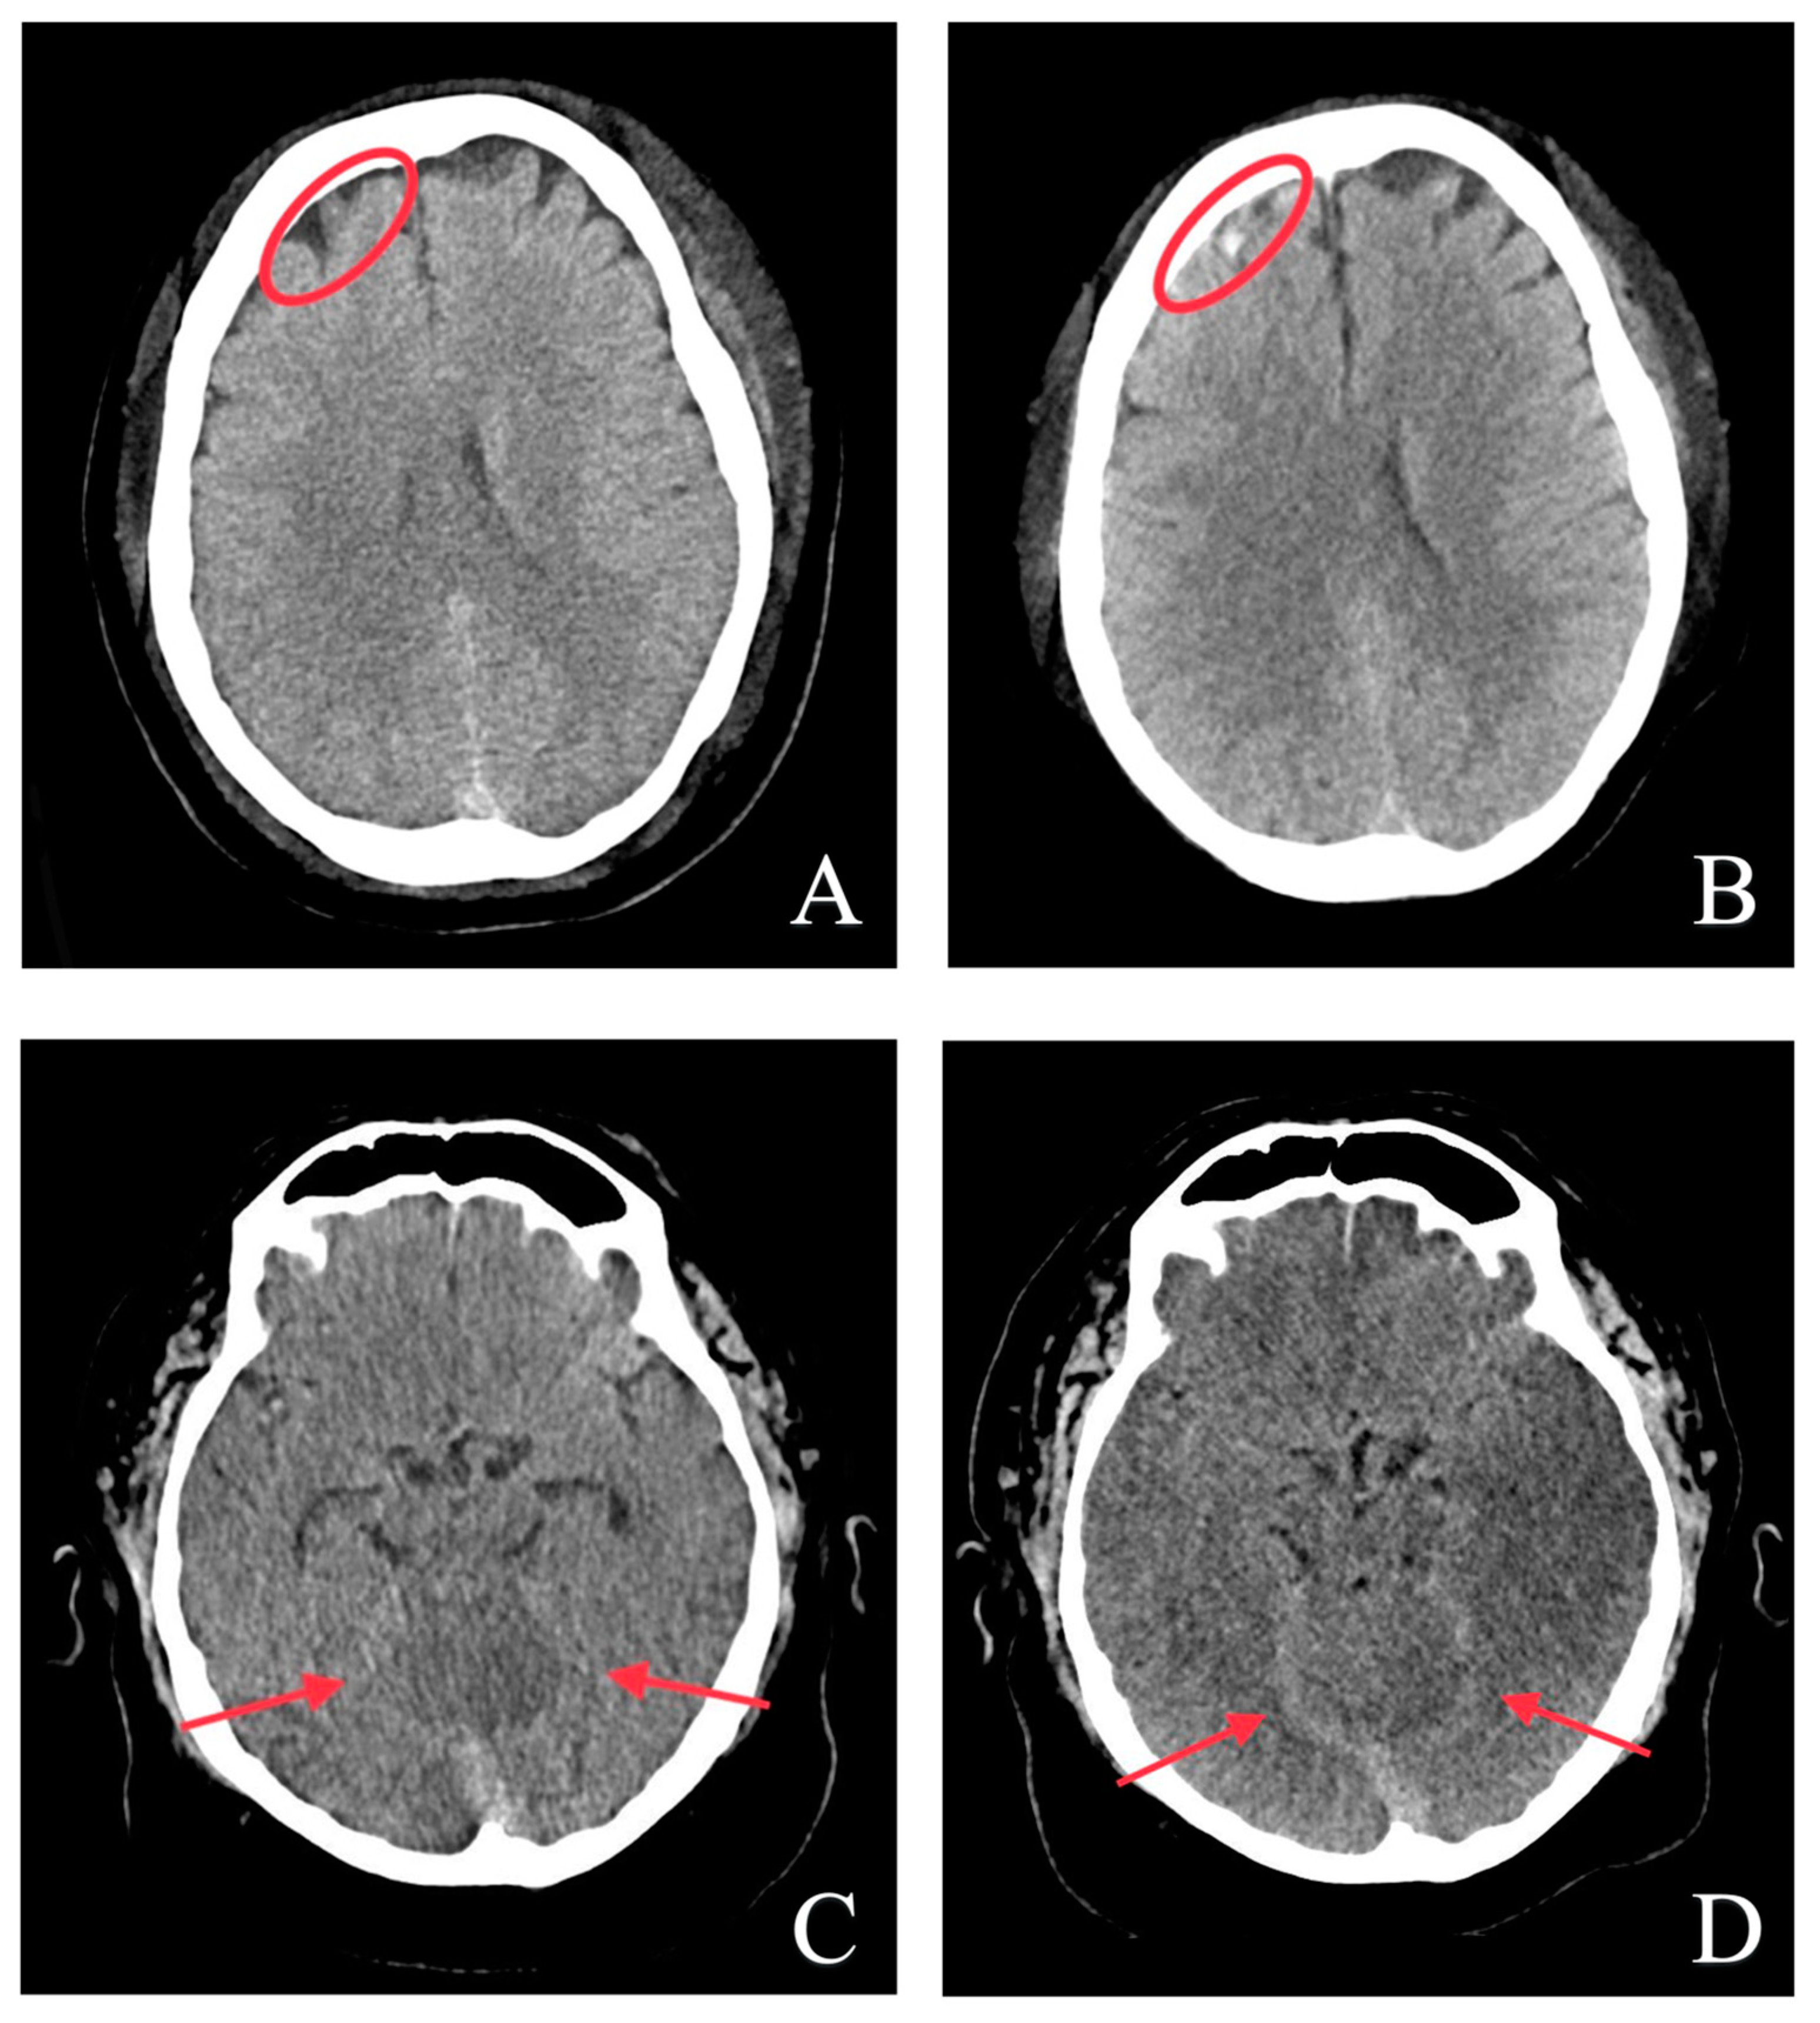

3.4. Automatic Brain Hemorrhage Analysis

4. Discussion